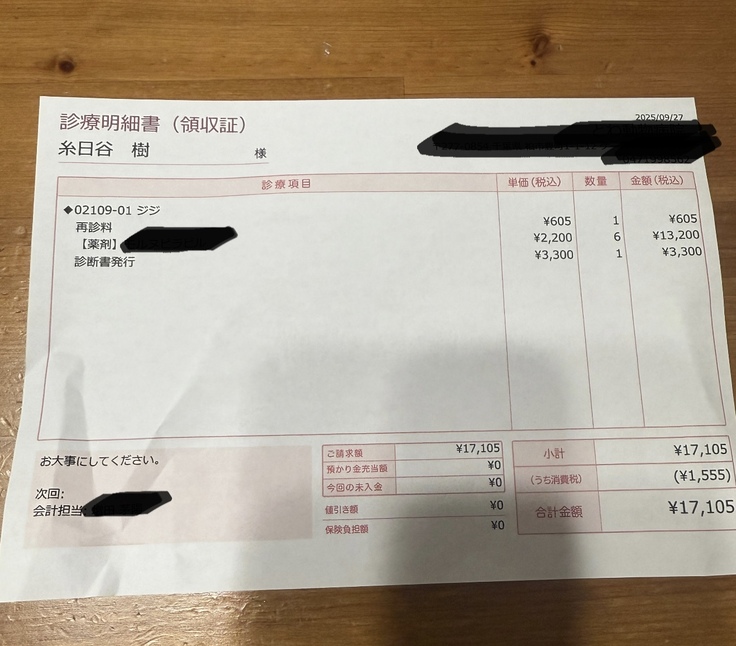

現時点までの治療費です⬇️

診察代、検査代、薬代の合計で210.386円

9/27▶️17.105円